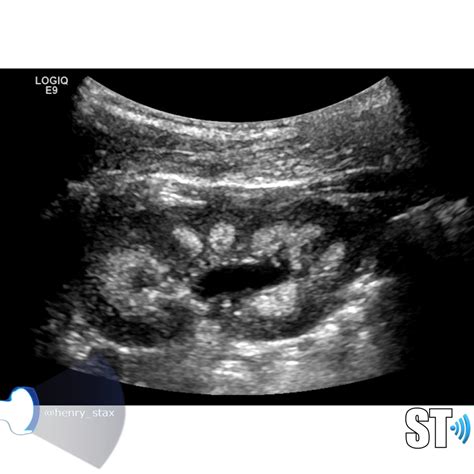

Ultrasound, or USG, is a non-invasive imaging technique that uses high-frequency sound waves to create images of the internal body structures. In the context of Medullary Sponge Kidney, USG plays a pivotal role in the diagnostic process. It helps in visualizing the cystic dilatation of the collecting ducts and assessing the overall condition of the kidneys.

Interpreting the results of a Medullary Sponge Kidney USG requires expertise in radiology. The key findings that indicate Medullary Sponge Kidney include:

• Cystic dilatation of the collecting ducts in the renal medulla.

• Enlarged kidneys with a spongy appearance.

• Presence of kidney stones or calcifications.

• medullary sponge kidney ultrasound images

• medullary sponge kidney ultrasound appearance

• sponge kidney ultrasound images